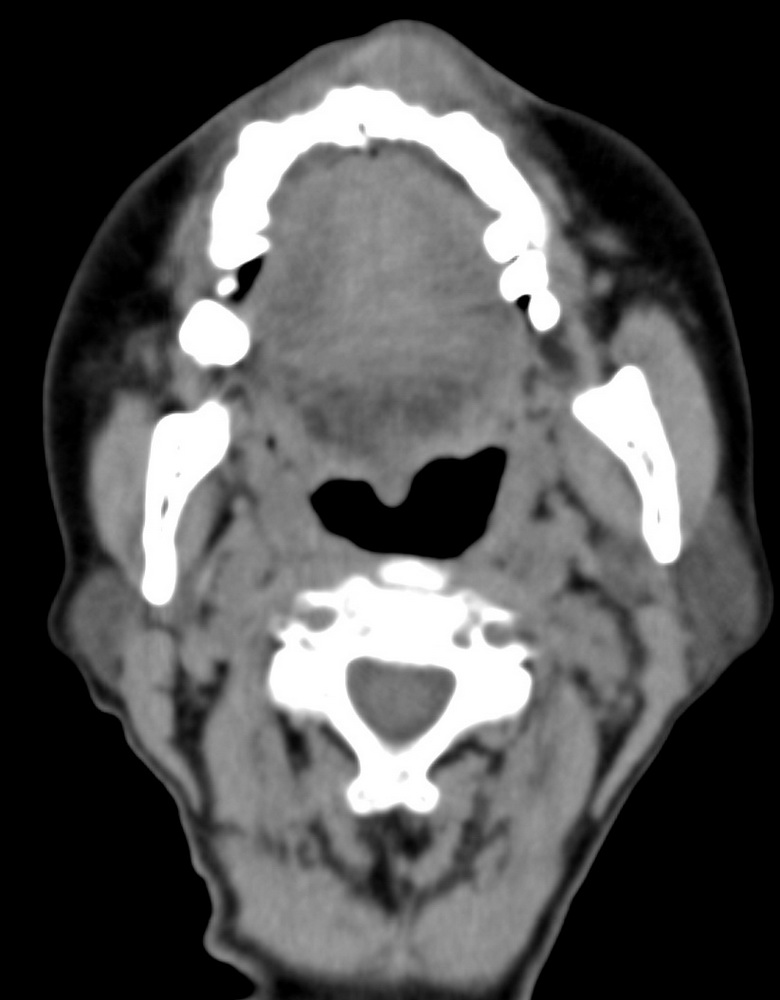

女,68岁。发现上唇无痛性肿块2年多,查体局部皮肤隆起,其余未见异常。

病灶ct值约42hu。

病理结果:唾液腺混合瘤。